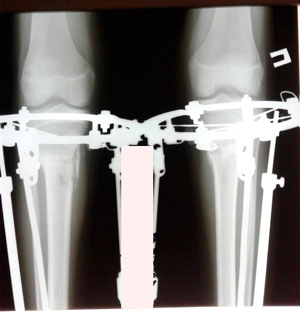

Дата операции - 15.06.2019г.